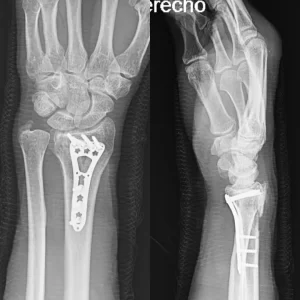

Placas para radio distal

RÁDIX Volar

Rádix Plus

Indicaciones

Fracturas en la porción distal del radio simples y complejas

con compromiso intra y extra articular.

Materiales

Titanio para implantes

Presentación Set

Volar Derechas e Izquierdas 2-3-4 Orificios.

Para usar con:

» Tornillo Cortical Autotarrajante 2.7 mm – Titanio

» Tornillo de Bloqueo 2.4mm – Titanio